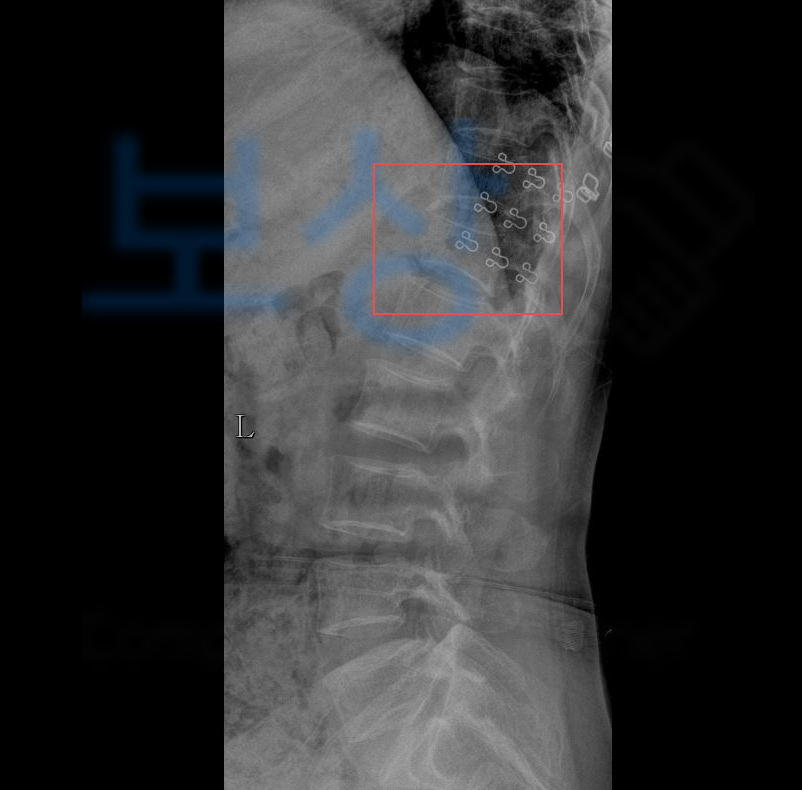

흉추 12번의 압박골절 S22070

진단을 받게 되었습니다.

흉추12번 을 의무기록지를 보면 많이들 T12라고 표기되어있는데요, 등뼈 (Thoracic vertebrae)의 약자로 T12 는 흉추12번 을 가리킵니다. 위 사고로 약물치료와 허리보조기 착용을 해야했던 상황..

척추의 골절 Thoracic vertebrae 골절